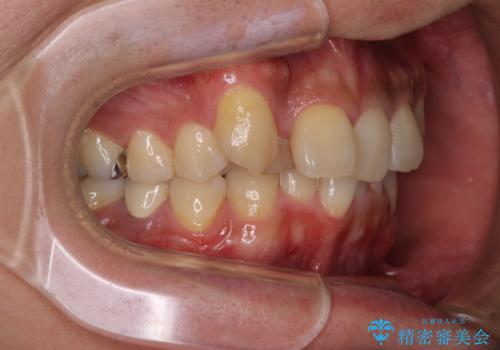

- 上顎の八重歯と正中のズレを気にして来院された患者様です。

八重歯による叢生は著しく、それにより上顎の正中が大きく右にずれている状態でした。

口元の突出感は感じていなかったことと、奥歯の咬み合わせを考慮し、上顎のみ左右の第一小臼歯を抜歯してワイヤー装置にて矯正治療を行うこととしました。

補助装置を併用することで効率的に八重歯や正中位置の改善を達成することができました。